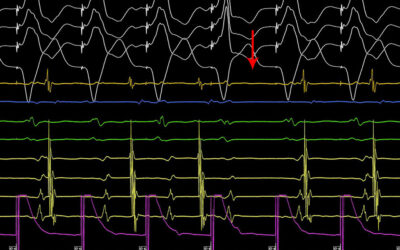

Στο βίντεο μας μιλούν για το νέο Κέντρο Καρδιάς και Αγγείων «Athens Heart Center» στο Ιατρικό Π. Φαλήρου ο κ. Ιωάννης Πυρνοκόκης, Γενικός Διευθυντής και ο δρ Απόστολος Κατσίβας, Καρδιολόγος- Αρρυθμιολόγος, Διευθυντής.